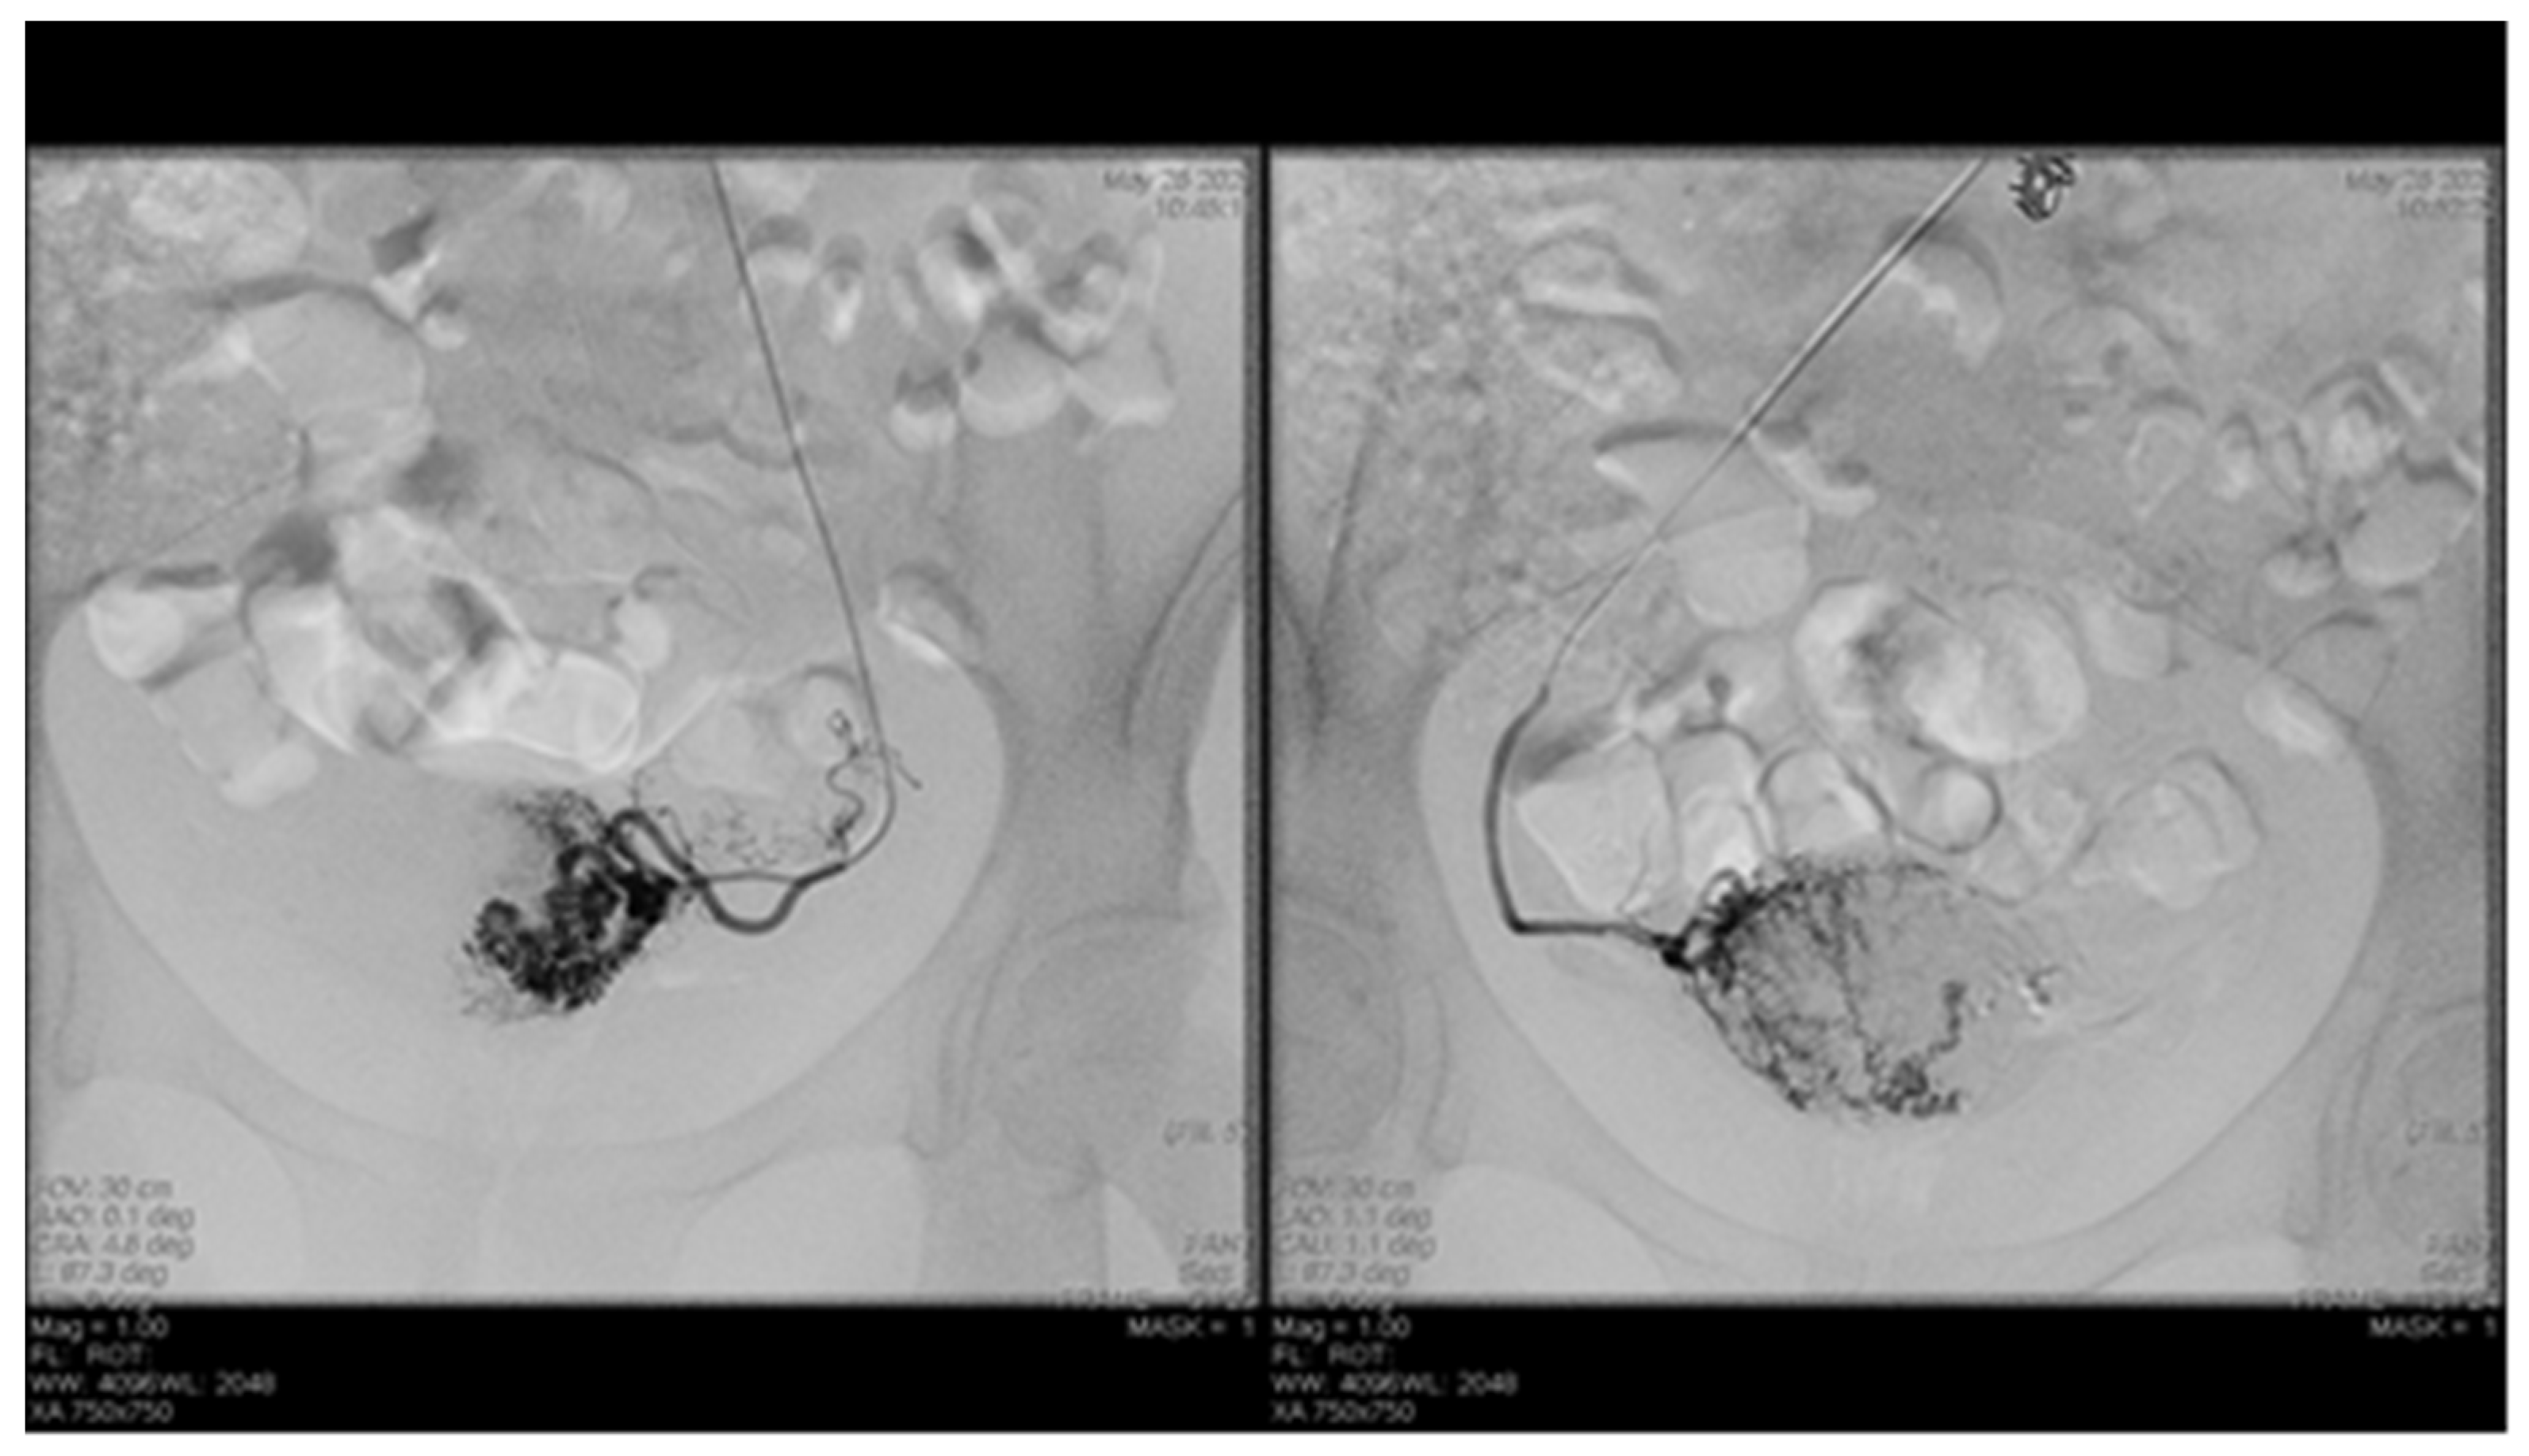

7.84% (n = 89) of the patients with cervix cancer needed supraselective embolization of cervicovaginal and long vaginal arteries, as seen in Figure 2 and Figure 3.

Endovascular procedures were used in 2.29% of cases with ectopic pregnancy (n = 26) (see Figure 4 and Figure 5), 1.23% of patients with arteriovenous malformation (n = 14) (see Figure 6), and 0.52% of patients with major hemorrhage of obstetrical causes (n = 6).

Figure 2. Selective artery embolization in patient with cervical neoplasia.

Diagnostics 12 01436 g002

Figure 3. Selective long vaginal artery embolization in patient with cervical neoplasia.

Diagnostics 12 01436 g003

Figure 4. Pelvic artery embolization for cervical ectopic pregnancy.